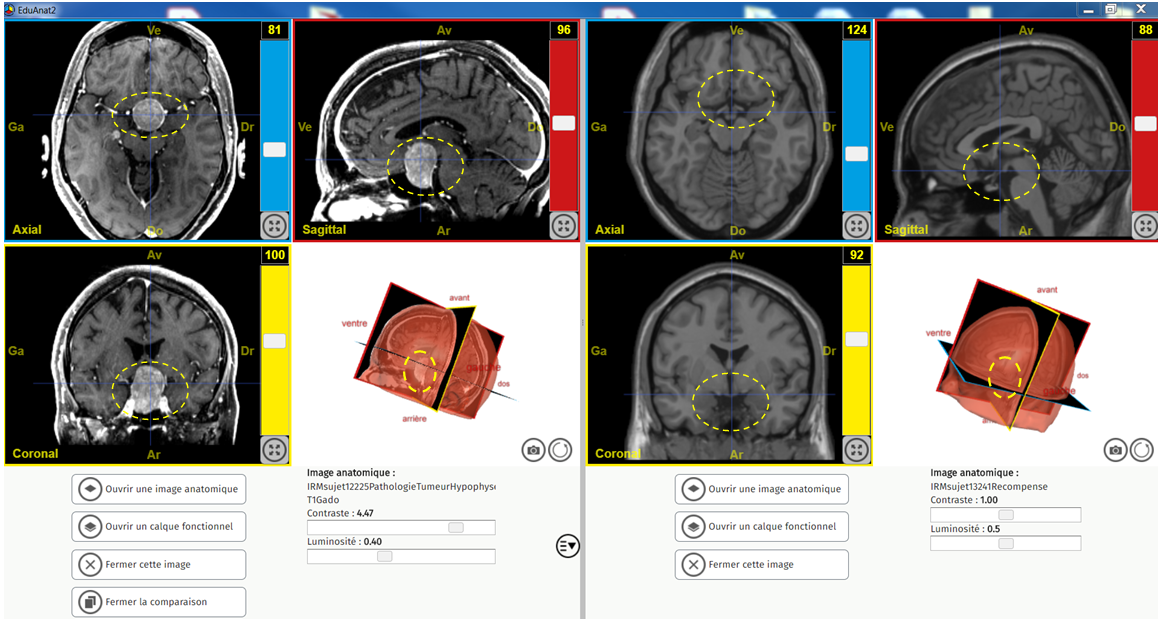

Comparaison Tumeur HypoPhyse et sain